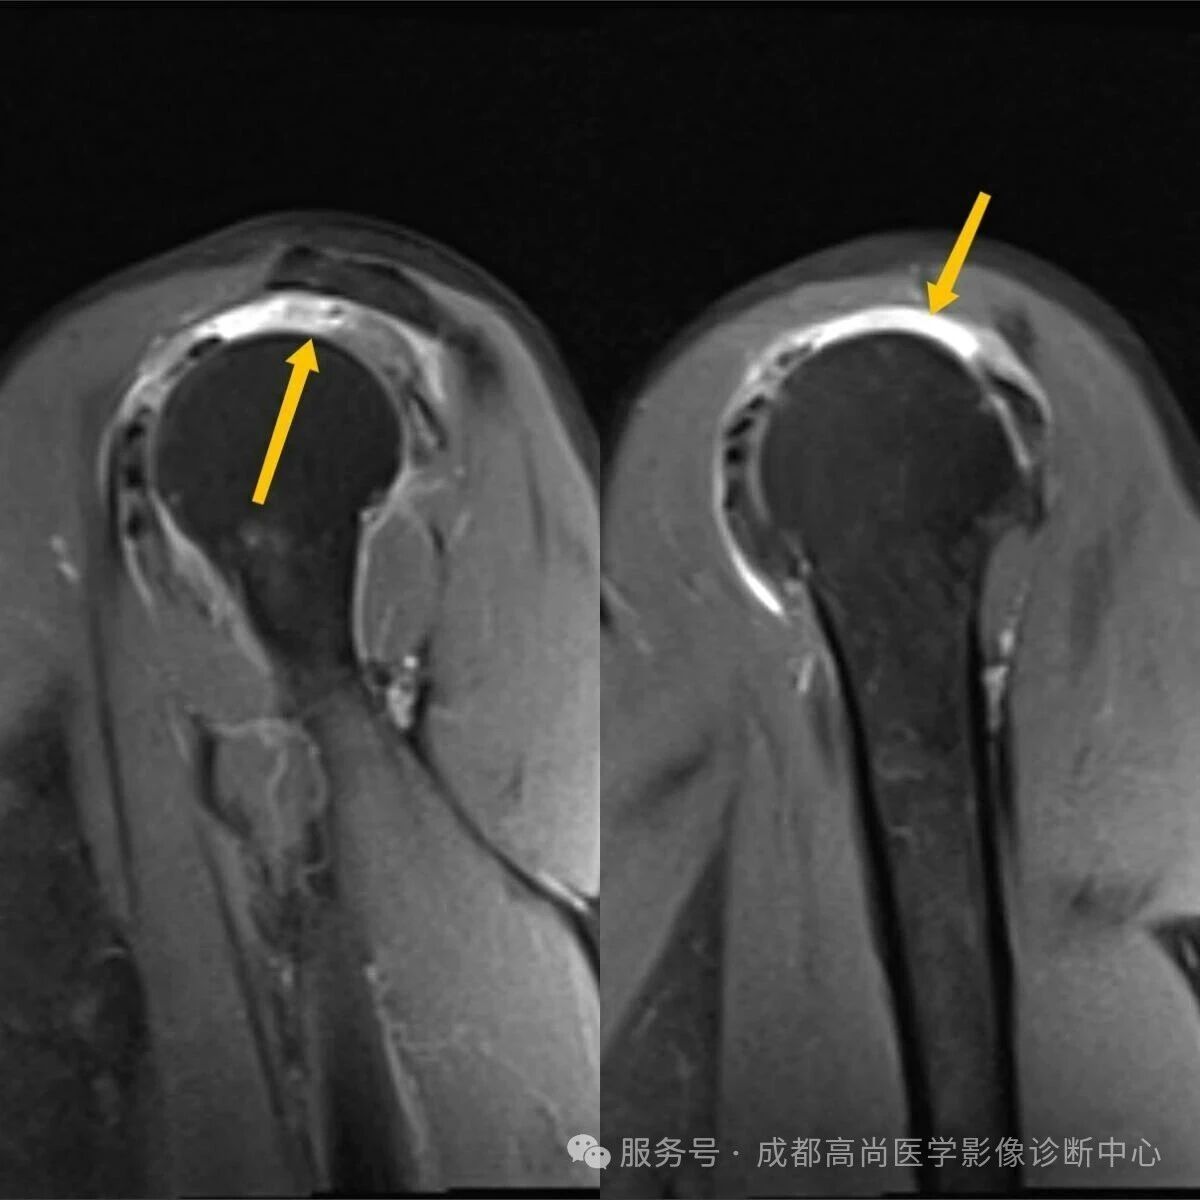

右肩 MRI 检查图像

图 1—5 MRI 平扫示右肩冈上肌肌腱失去正常形态结构,局部显示欠连续,肌腱附着点未见正常结构显示,提示冈上肌腱断裂。

A. 正常冈上肌腱前部;B. 正常冈上肌腱中部层面;C. 冈上肌腱变性;D. 冈上肌腱中部完全撕裂;E. 冈上肌腱滑囊面部分撕裂;F. 冈上肌腱关节面部分撕裂